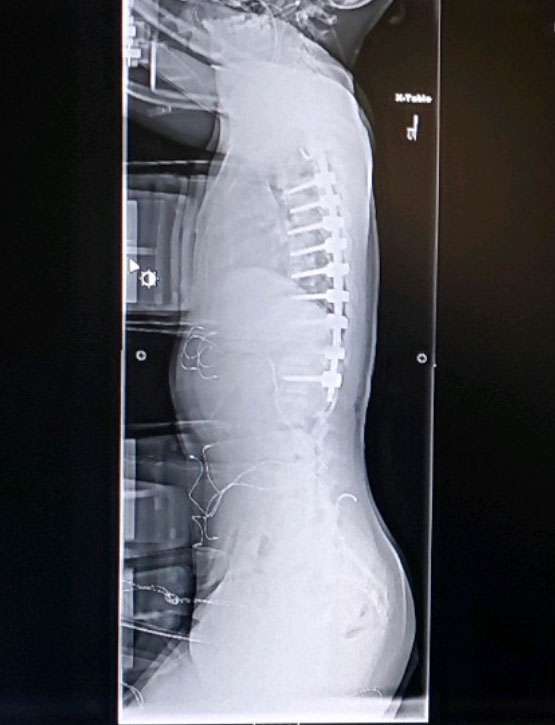

The brace was so unbearable to wear, that I would cry every time I put it on. I was told the brace wouldn’t fix my problem, but it would hopefully stop my spine from getting worse. I didn’t want to wait until I was 18 because I didn’t want to risk my spine getting worse, and having my movement become limited in the future. So, my last two options were to get a Spinal Fusion or a Vertebrae Body Tethering (Tethering/VBT). A spinal fusion is a surgery where bolts and rods are placed in your spine to keep it aligned, while Tether is a “rope” that is attached to screws on the vertebrae which goes along the side of the spine to keep it aligned.

My biggest fear was getting a Spinal Fusion because I didn’t want my spine to be completely fused from my thoracic to my lumbar because my motion would be limited. Luckily, I was told they would only have to fuse my thoracic, and hopefully my lumbar will follow as I grow. I would still be limited, but the change wouldn’t be so drastic, and there was still a possibility that my lumbar could get worse. After a few more days to think about the decision, we scheduled the appointment and I was due for surgery on December 16, 2020.